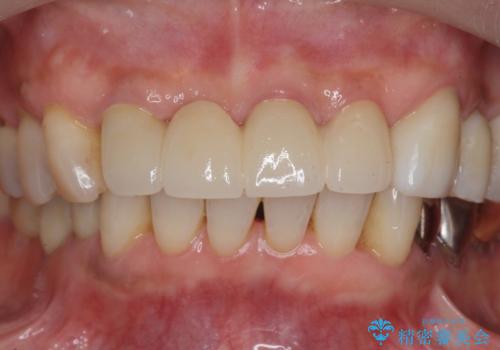

3. ぐらつく前歯 ブリッジ治療の治療後